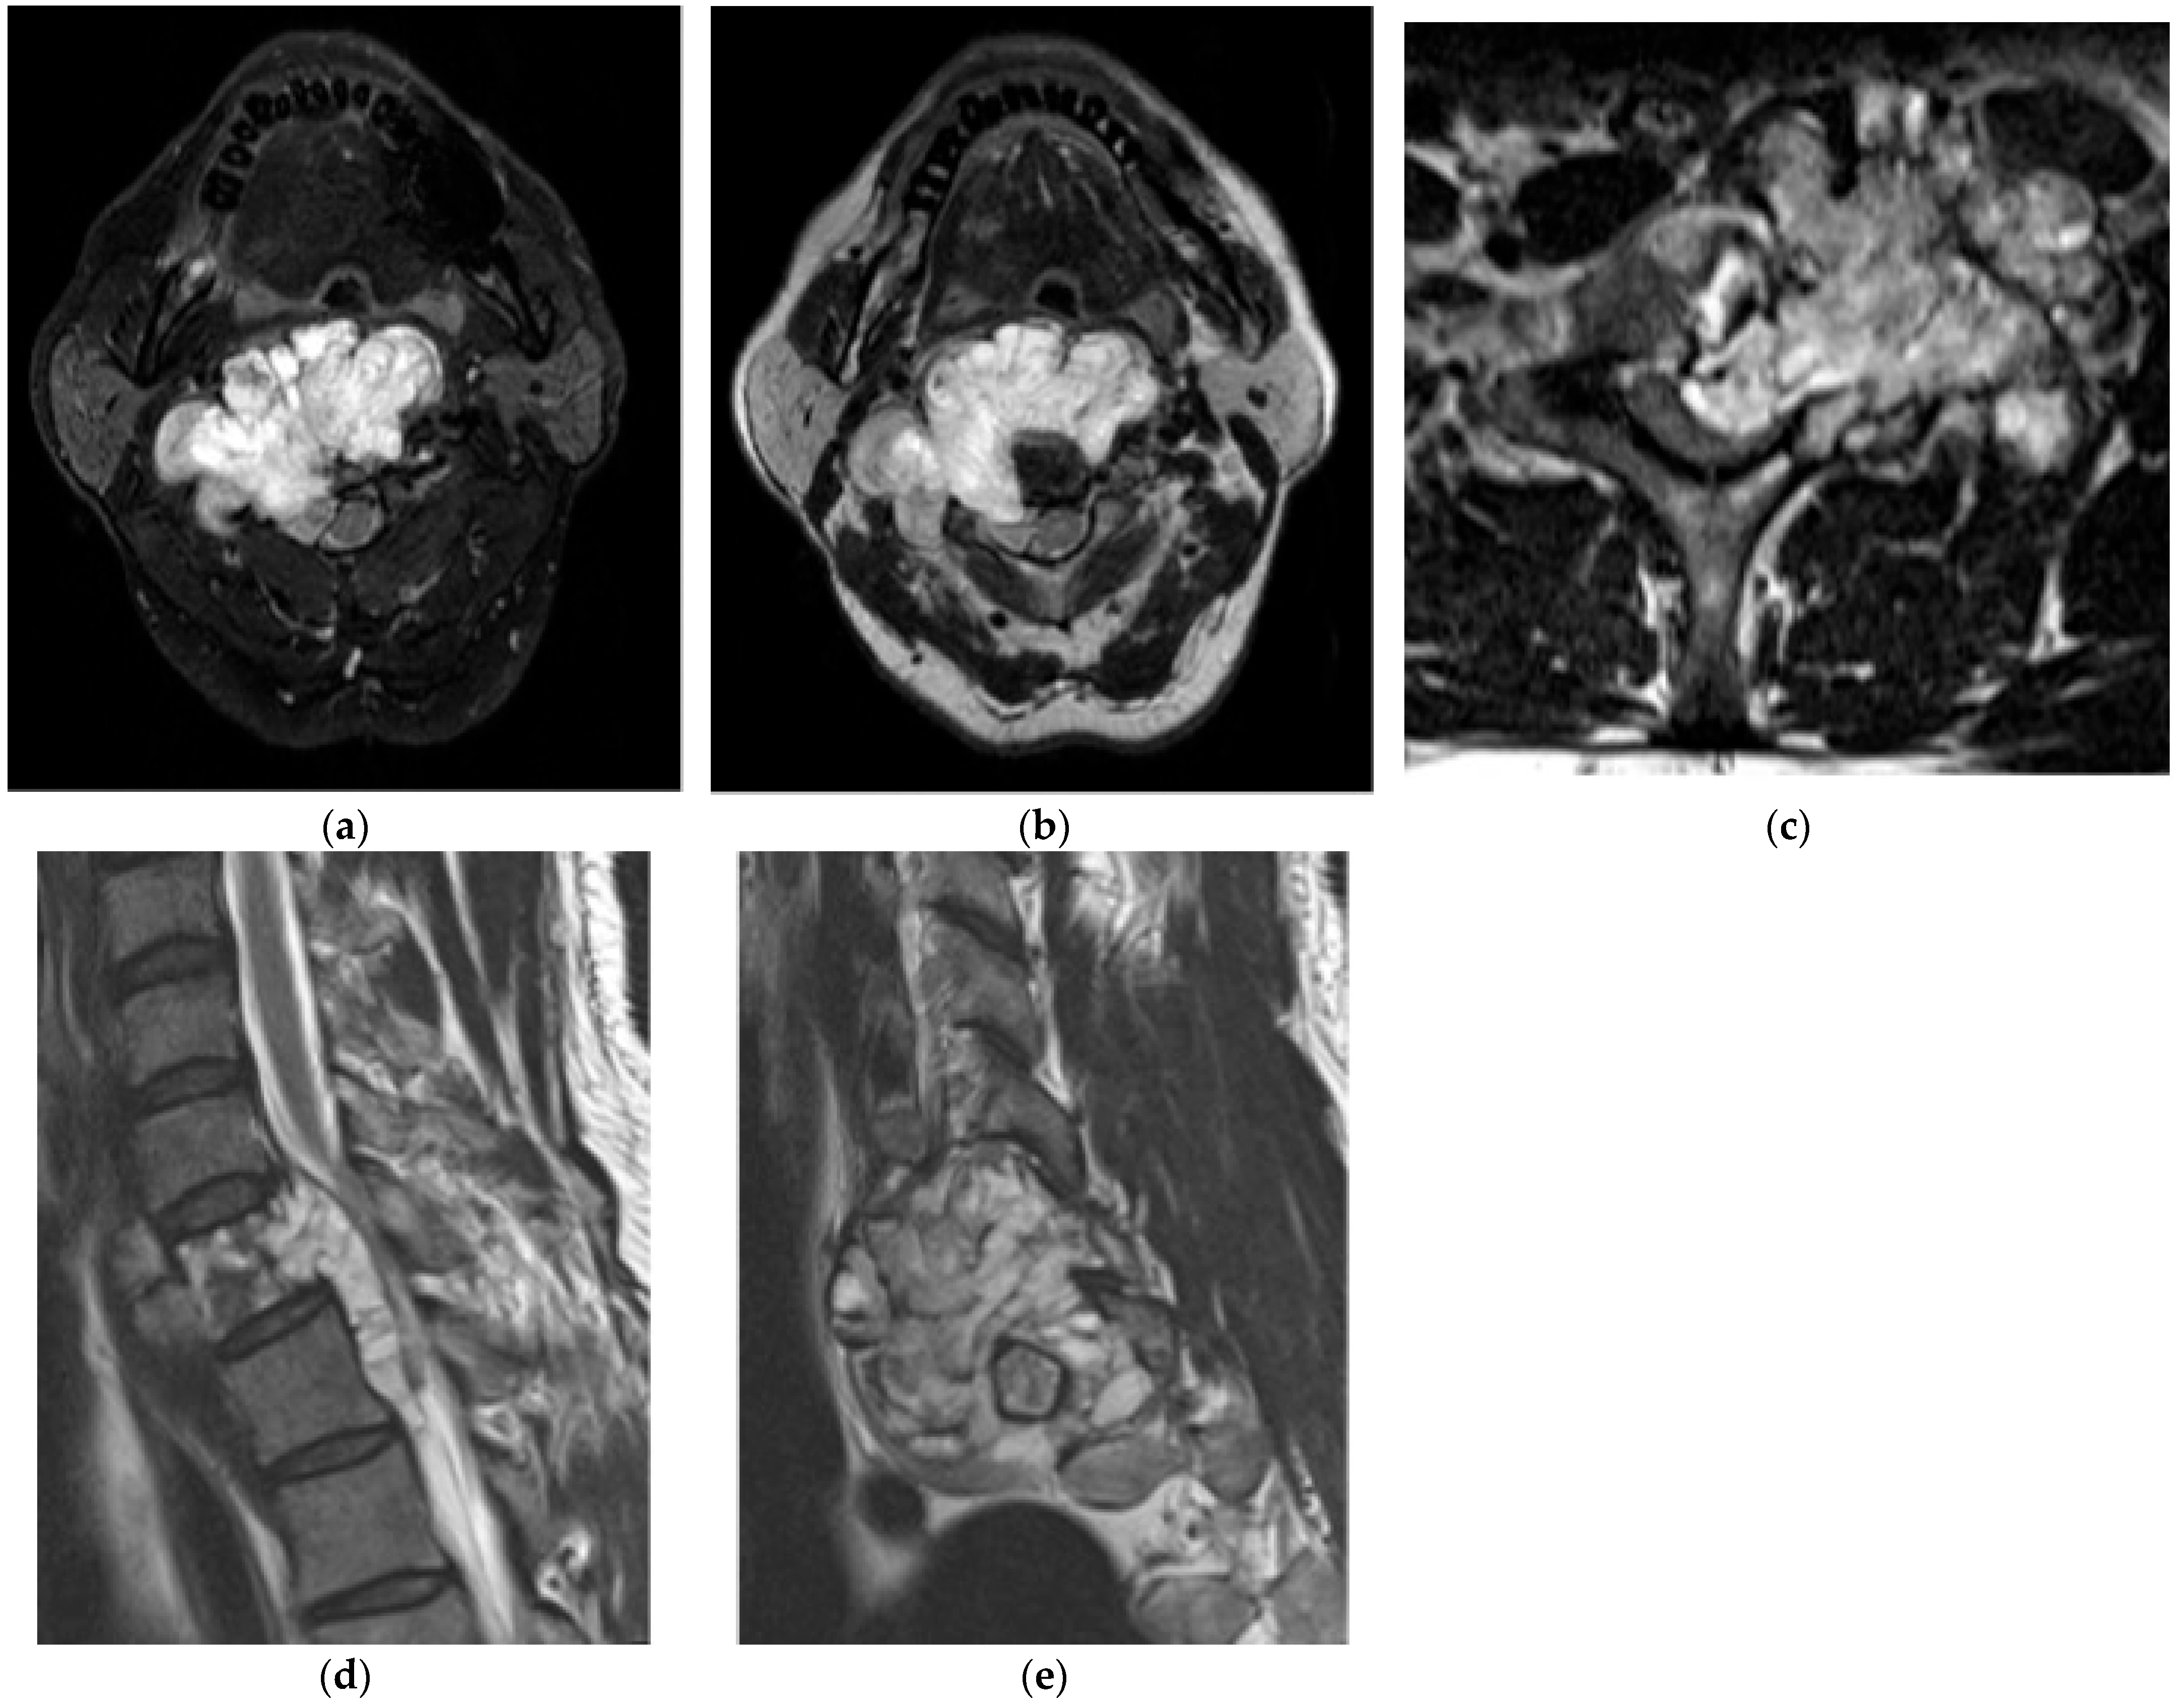

2.1.3. Osteoblastoma

2.5.2. Aneurysmal Bone Cyst

2.6. Fibro-Osseous